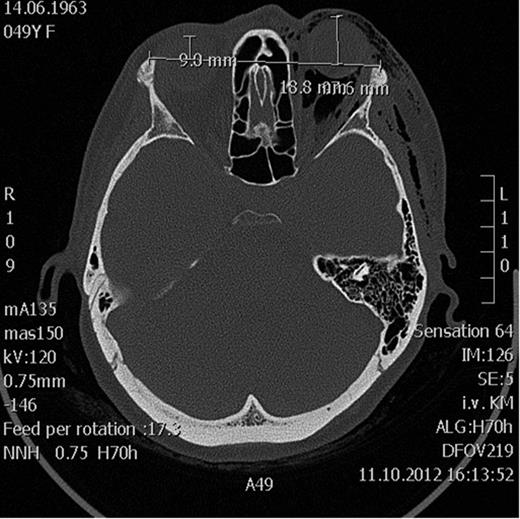

Spiral computed tomography (CT) was performed using 1 mm slices with a soft tissue and bone algorithm. A non-dislocated orbital floor fracture and a large amount of intraorbital emphysema were found, especially retrobulbar between the ocular muscles and around the optic nerve, causing exophthalmos (the distance from the corneal apex to the line connecting orbital rims was 18.8 mm; normal 9.0 mm) (Figs 1–2).

Axial CT scan showing massive emphysema of the orbit leading to proptosis.